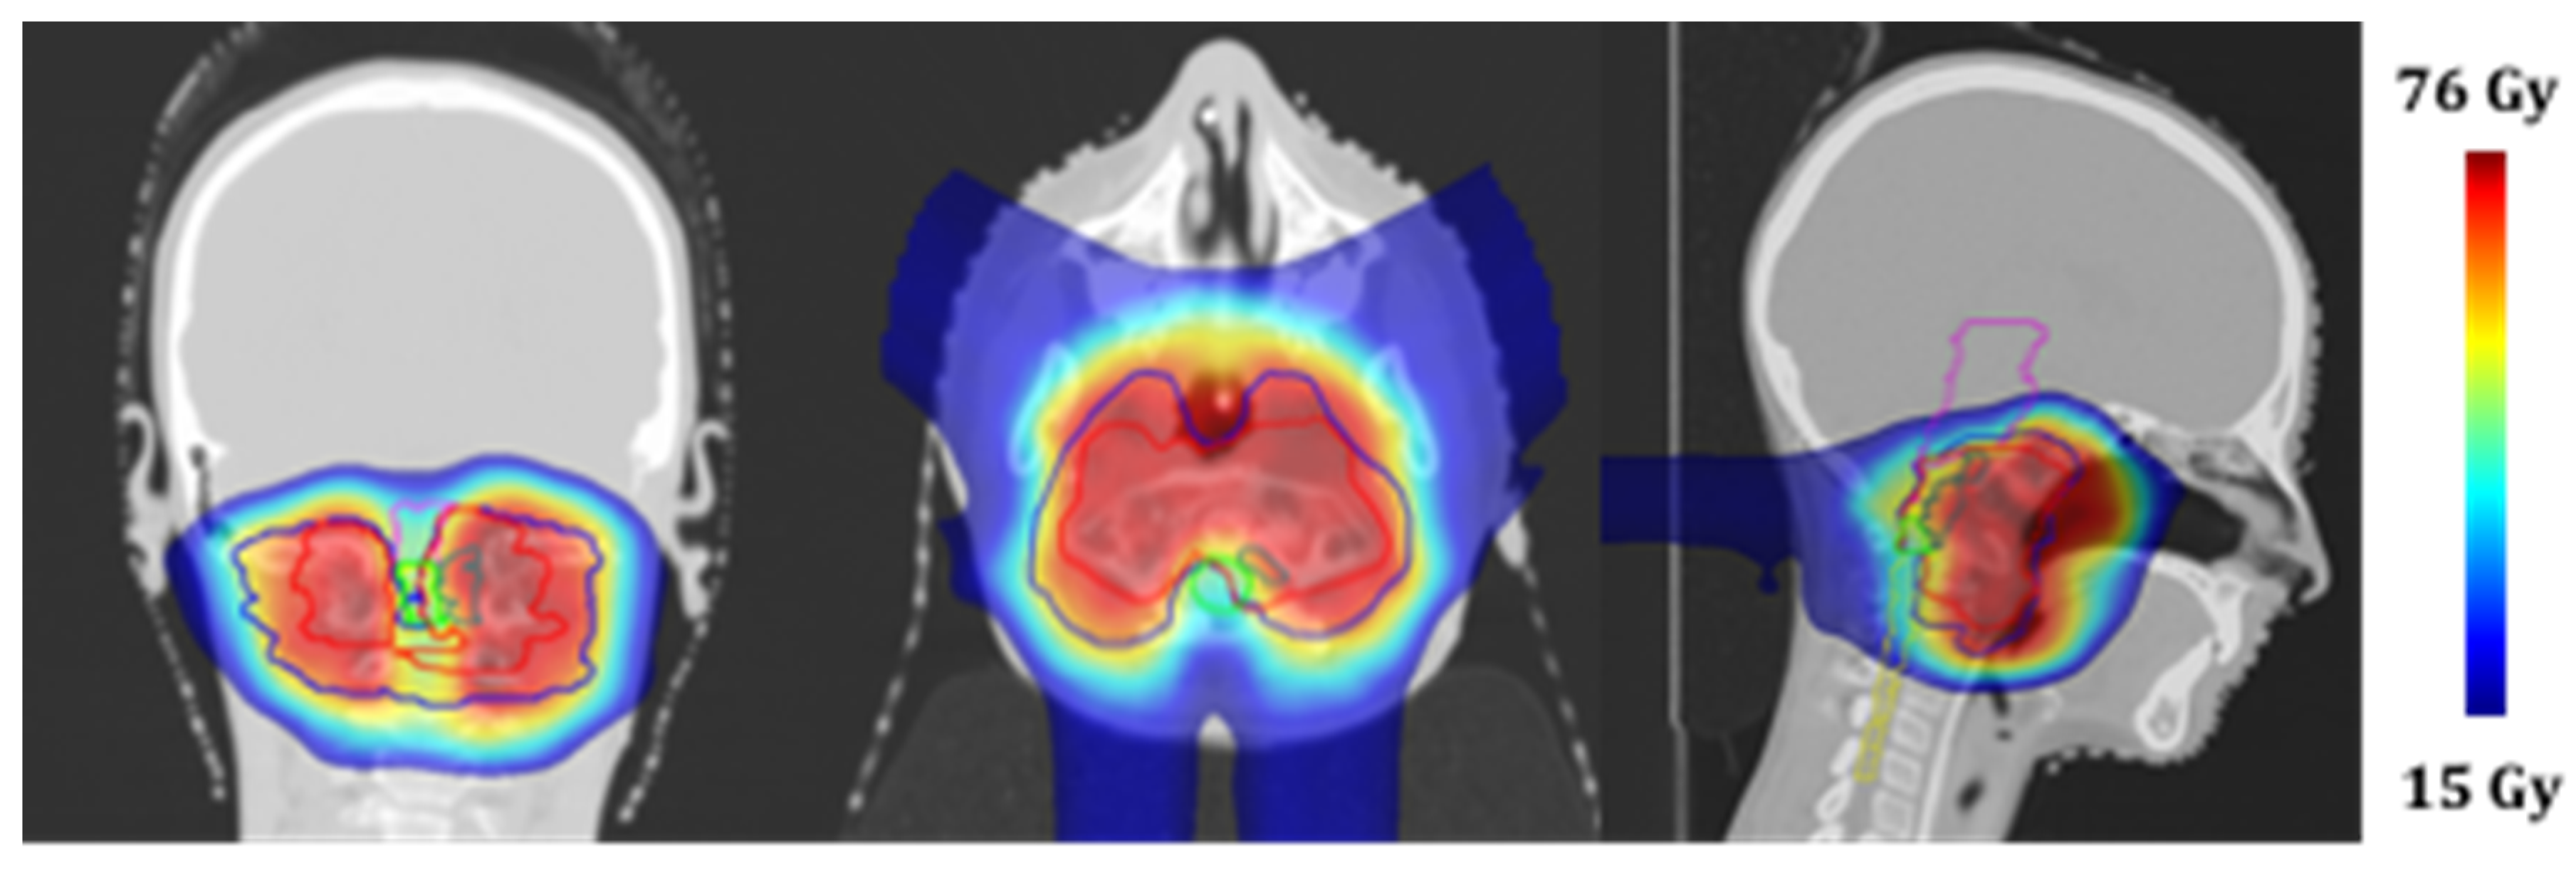

Four MRI examinations (T2-weighted sequence, without contrast) were acquired over the treatment course at doses of 32.4, 54, 64.8, and 73.8 GyRBE, respectively (Figure 4).

The figure shows temporal sequence of T2-weighted MR axial images of the nodular component at different times. The upper-left image represents the situation at diagnosis, while the others (clockwise direction) show the evolution during the treatment.

The bony component of the lesion around the tooth of the axis did not change in volume or morphology over the course of treatment, whereas the nodule component showed a progressive dimensional modification from 2.323 cc at the beginning of the treatment to 2.829 cc at 32.4 Gy RBE, 2.051 cc at 54 Gy RBE, and 1.045 cc at 64.8 Gy RBE and 73.4 Gy RBE (Figure 5). This led to a total reduction from the beginning to the end of proton therapy of 1.278 cc (about 55% of the initial volume). This reduction allowed the decompression of the spinal cord.

The early response of this nodular component of chordoma was an unexpected finding during the irradiation, which should be described as an early therapeutic response. Such a result is even more meaningful considering that this tumor area received less than prescribed dose because of its proximity to the spinal cord. At the same time, although the dose to the spinal cord was constrained to 54 GyRBE, thanks to the quality of the treatment plan, at least 50% of this tumor area received 70 GyRBE. This may justify the good radiological outcome.

Figure 4. Treatment monitoring over the proton therapy course with T2-weighted MRI.